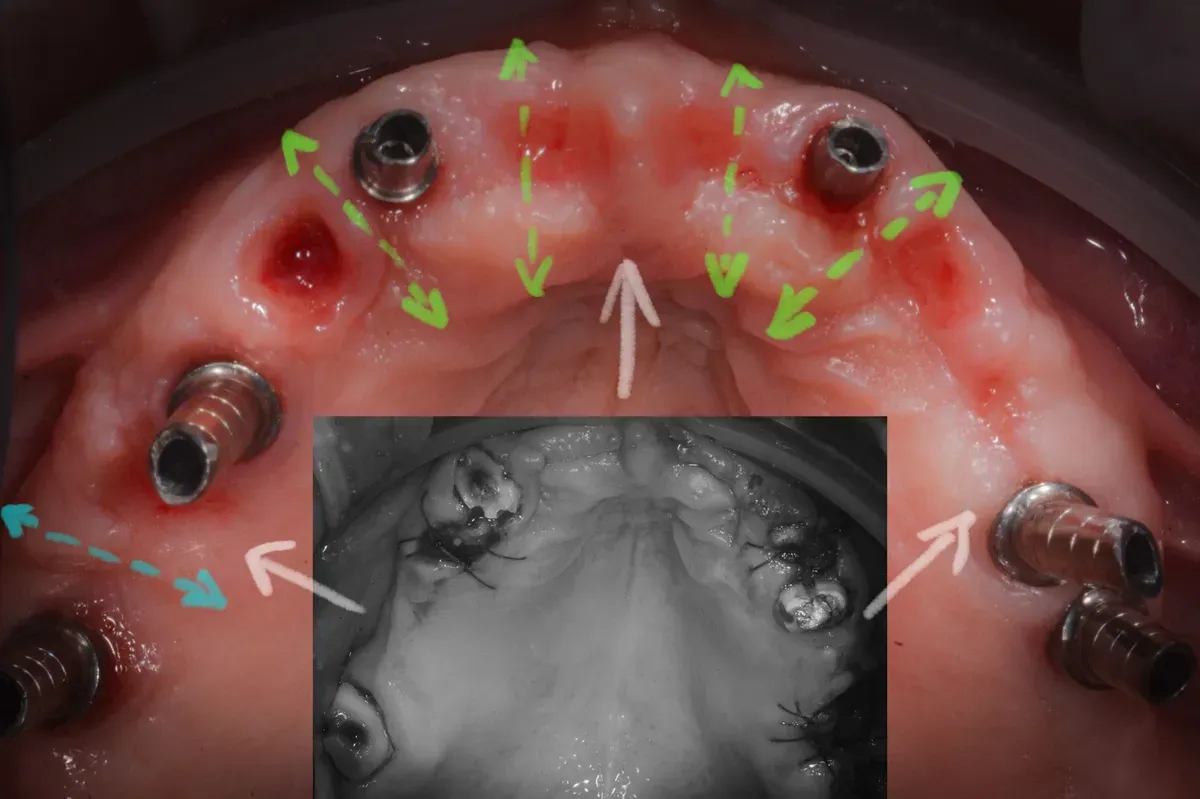

L’immagine mostra l’espansione osteo-mucosa con l’inserimento di due impianti nella pre-maxilla, in posizione 1.2 e 2.2.

Lo spazio lasciato vuoto guarirà con formazione di nuovo osso e mucosa cheratinizzata.

Il confronto tra le immagini cliniche prima e dopo il trattamento (vedi sotto) è impressionante e non lascia spazio a dubbi sull’efficacia delle tecniche di espansione osteo-mucosa.

L’aumento delle dimensioni effetto della rigenerazione

Le due immagini sembrano appartenere a due persone diverse: la dimensione trasversale e la cresta alveolare anteriore sono entrambe notevolmente aumentate, suggerendo una significativa variazione anatomica.

Inoltre, è impressionante notare che tutto questo aumento è stato ottenuto senza alcun tipo di innesto, il che sottolinea la capacità naturale del corpo di modificarsi e crescere in risposta agli stimoli chirurgici della guarigione per seconda intenzione.